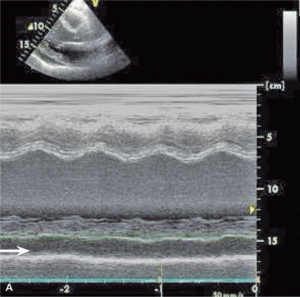

U chorych z płynem w worku osierdziowym obserwujemy mały woltaż załamków w EKG (ryc. 1), szczególnie charakterystyczny dla dużych wysięków lub tamponady. Niekiedy stwierdza się obniżenie odcinka PQ i zmiany ST-T. Tamponadzie towarzyszy zwykle naprzemienność elektryczna, która na ogół wiąże się z obecnością dużej ilości płynu [10].